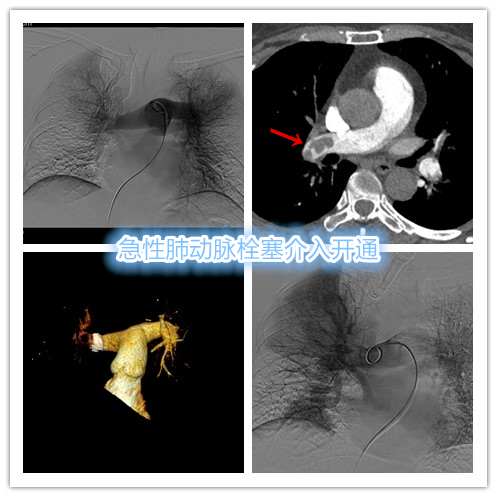

(1)肺动脉介入开通:如留置溶栓导管溶栓、导管抽栓、机械碎栓等介入微创手段治疗,尤其适合急性肺动脉栓塞,血液流动学不稳定,有静脉溶栓禁忌者。

综合考虑为下肢深静脉血栓脱落导致急性大面积肺动脉栓塞,患者出现血压、血氧饱和度下降,血液流动学不稳定。遂即行急诊肺动脉溶栓、碎栓治疗,下腔静脉滤器植入预防肺动脉栓塞复发。

肺动脉导管溶栓+碎栓治疗

经急诊介入治疗后患者生命体征明显改善,血压回升、心率减缓,血氧饱和度100%,复查造影显示右中、下肺动脉主干及左下肺动脉主干均已明显通畅,肺部血流灌注明显改善,术后继续系统抗凝治疗,恢复良好。